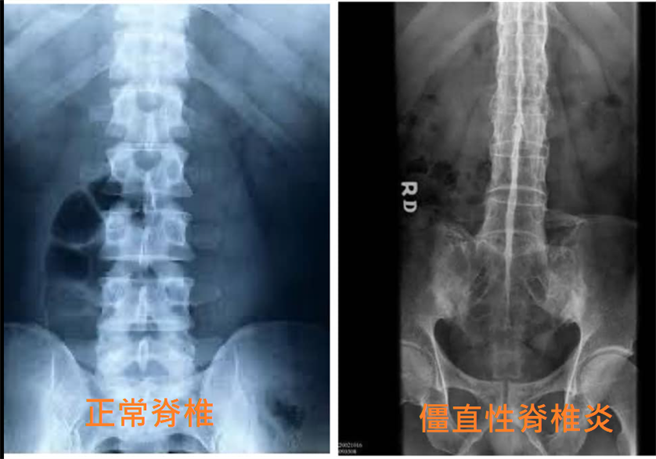

直到有护理师放上一张X光片对比正常脊椎以及僵直性脊椎炎的结构,真相才告水落石出,大师兄看到僵直性脊椎炎X光片立刻回应「没错!我看到的就是这种的!」、「这事保证真的,那条脊椎整条黏到我想拍照留念,真的是没有缝隙,真不知道为什么烧出来会这样......而那个人生活起来我想应该超级不便吧」。

大师兄在PO文中认真的求问,「一般来说,火化出来的脊椎都是一节一节分开的,有一天,我捡到一整条脊椎,他是完整而且黏在一起的,就是完全没有骨头间的缝隙,整条脊椎立起来都不会分开,看起来真的蛮诡异的」。他还为此去询问前辈学长,「学长告诉我这个叫做『僵直性脊椎炎』,真的是这种病吗?要是脊椎没缝隙,生活上面有什么不便吗?」